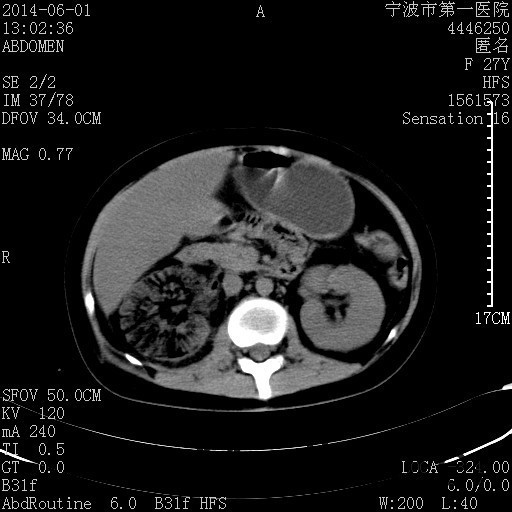

患者,女,27岁,因“右下腹疼痛伴呕吐2天”入院 患者无明显诱因出现右下腹疼痛伴呕吐、发热,体温最高39度,急诊CT示:右肾集气,考虑气性肾盂肾炎。

查体: 右肾区叩击痛,右下腹压痛,无反跳痛。 辅助检查: 空腹血糖9.7mmo/L,餐后血糖18mmol/L 血常规:白细胞 11.3*109/L, 中性百分比 77.4%, 血红蛋白 8g/L, 血小板 319*109/L 尿常规 WBC+++ 生化:白蛋白 37.5g/L,肝肾功能正常 泌尿系CT:右肾集气

诊断为“气性肾盂肾炎,感染性休克,糖尿病酮症酸中毒” 血、尿、脓液培养均示“克雷伯杆菌” 入院第2天行“右双J管置入术” 入院第3天、7天行“右肾穿刺造瘘术” 入院1月行“右肾切除术” 术后顺利康复出院。